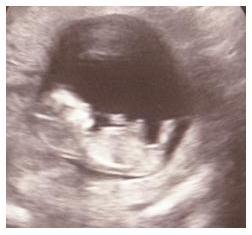

Monatsforum Juli Mamis 2012

Bild zu Foto 3 - Forum für Juli - Mamis